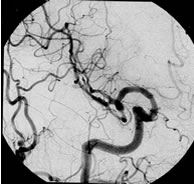

脳動静脈奇形

治療成績は病変の大きさ及び部位によって大きく異なりますが、直径3cm以内のガンマナイフ治療に適した脳動静脈奇形の場合、3年後の完全閉塞率(治癒率)は60−90%前後と報告されています。下図はガンマナイフ治療が奏功し、完全閉塞した典型的な症例です。

3年後

![]() |

| 正面像 | 側面像 |